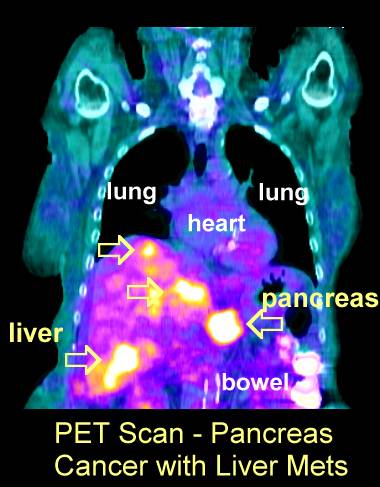

PET scans will show the cancer much better than with a CT (go here)       PET Scans: #1 , #2, #3, #4, #5, #6, #7, #8